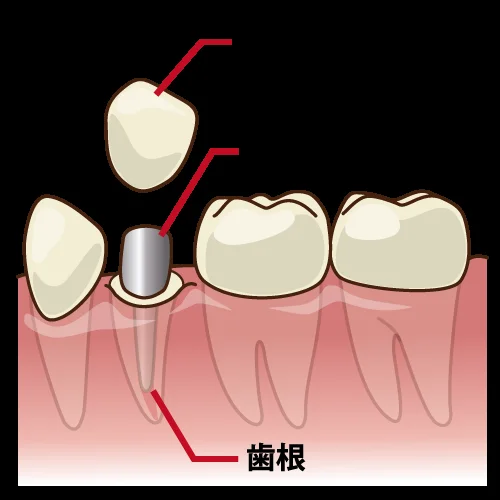

神経の治療後をセラミックで。

こんにちは。 雪国の方ではもうすでに雪が結構降ってるようですね。 ここしばらく暖冬でウィンタースポーツもあまりできない状況でしたが、今年はしっかりと楽しめそうでよかったです。 また、今月は息子の行事で土曜日の休診日が多くなっております。..…

虫歯の治療後セラミックの被せ物に。

こんにちは。 現在当院では歯科衛生士を募集しております。 もし気になるなという方がいらっしゃいましたら、是非お電話やHPの問い合わせからお問い合わせいただけると幸いです。 さて、ここ最近遠方からの初診の方や歯科医療従事者からの問い合わせが非…

セラミックの被せ物

こんにちは。 最近また少しずつ体重が増えてきてしまっているので、少しずつ落とさないとなと思っています(⌒-⌒; ) まぁ無理なダイエットは体に悪いので、無理のない範囲でジリジリとですね・・・! さて、ここ最近遠方からの初診の方や歯科医療従事…

CAD/CAM冠について

こんにちは。 そういえば、今更ですが・・・ パラジウムの高騰を受け、当院でもCAD/CAM冠の届け出を出しました。 今日はそのCAD/CAM冠について書いていきたいと思います。 そもそもCAD/CAMとは何ぞやって所からですが・・・ Com…

続きを読む →